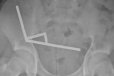

由于吞下近200块强力磁铁,新西兰一名13岁男孩经手术切除了部分肠道。